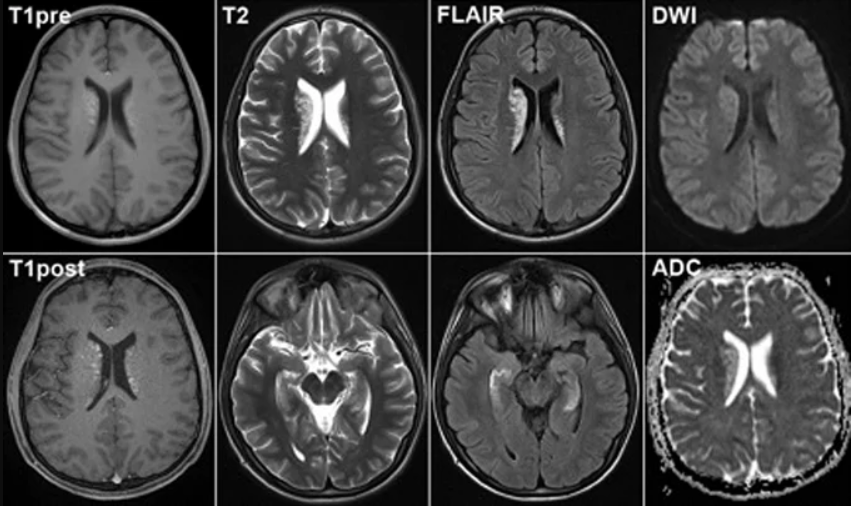

Магнітно-резонансна томографія (МРТ) – це медичний інструмент, який використовує потужний магніт, радіочастотні хвилі та комп’ютер для отримання чітких зображень внутрішніх органів. Процедура, що виглядає натисненням кнопки, але завдяки якій лікарі можуть проникнути до найглибших, найпотаємніших куточків людського тіла.

- МРТ без контрасту: чудово підходить для загального обстеження. Добре для початку, для швидкого огляду без зайвих ускладнень.

- МРТ з контрастом: тут уже інша справа, серйозніше. Підходить для виявлення пухлин, судинних аномалій і інших “злидників”, які ховаються вдало.